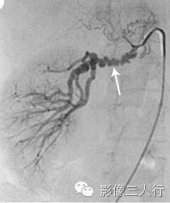

小脑发育不良性神经节细胞瘤的MRI诊断